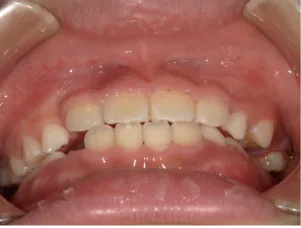

治療中⑥小4(10y2m):モノブロック装置継続中 上下正中改善中

治療中⑦小5(11y3m):モノブロック装置継続中

治療後⑧小6(12y3m):モノブロック装置継続中

咬み合せも安定していて、口元の突出・口唇閉鎖不全も改善